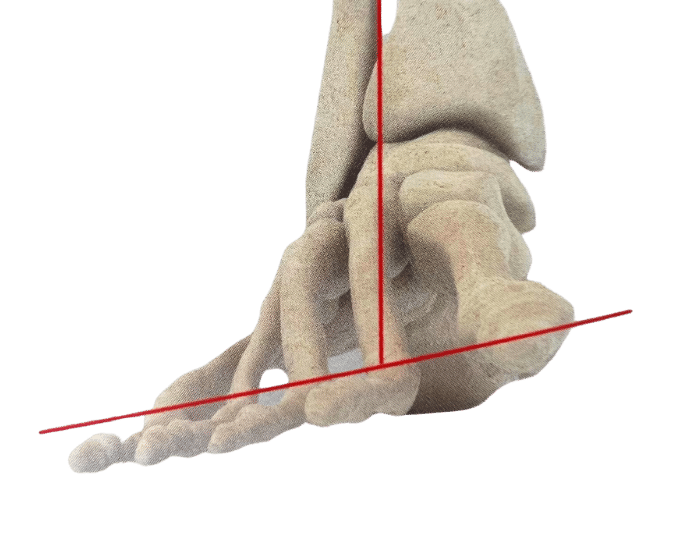

There are numerous reasons why you might need Custom Foot Orthotics. If you have pain in your foot, heel, knee or hip, have high arches or flat feet; or just being regularly on your feet and are getting any aches or pains in the feet or legs, or suffering from general foot pain while walking, running, playing sports or even at rest you qualify for Custom Foot Orthotics.